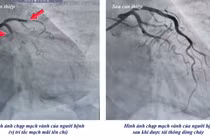

Bệnh nhân nhanh chóng được chuyển can thiệp chụp mạch vành và đặt stent động mạch vành cấp cứu, kịp thời tái thông dòng máu nuôi tim, qua cơn nguy kịch.